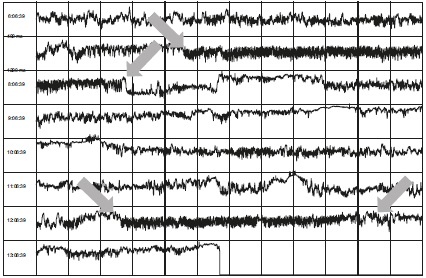

Взгляните на рисунок 7.4 с еще тремя примерами. Эти студенты поддерживали сердечную когерентность длительные периоды времени. Если посмотрите внимательно, вы увидите, что сердца всех студентов реагируют на устойчивое состояние возвышенных эмоций в течение как минимум 45 минут – то есть их тела реагируют на новый разум. Я бы сказал, что это довольно-таки сверхъестественно.

Иллюстрация к книге — Сверхъестественный разум. Как обычные люди делают невозможное с помощью силы подсознания [i_045.jpg]

Рисунок 7.4